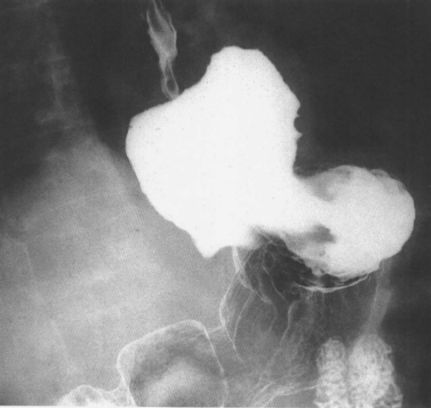

滑动型食管裂孔疝

食管旁型食管裂孔疝

可能你觉得这些图像太多,使得记忆分散,下面一张图包含了4种食管裂孔疝。